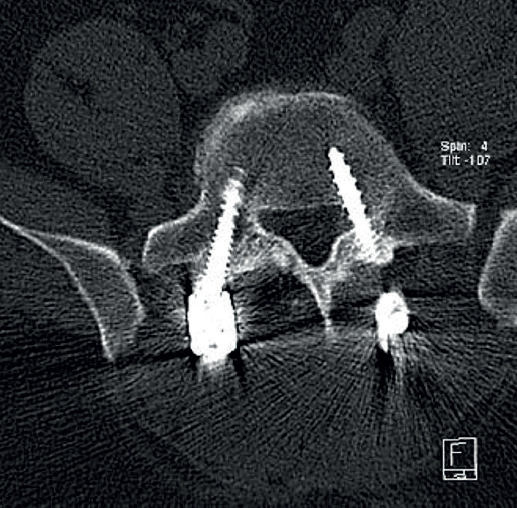

Cincuenta días tras el accidente se realizó fusión lumbar instrumentada L4-L5 con inserción de dispositivo intersomático por vía transforaminal derecha. En el segundo día postoperatorio presentó empeoramiento del dolor, objetivándose en la tomografía computarizada (Figura 2) malposición del tornillo L5 izquierdo que invadía el canal. Se reintervino a los 5 días corrigiendo el trayecto del tornillo. Sin embargo, persistió el dolor. La revaluación del caso, sumada a los hallazgos de EMG, motivó estudios complementarios de pierna y trayecto ciático (Figuras 3 y 4), detectándose una masa tumoral en el fémur izquierdo compatible con sarcoma fusocelular.